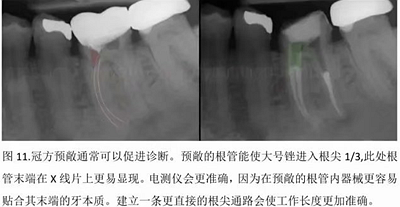

本文的目的是描述一種旨在優(yōu)化根管根尖部分預(yù)備的預(yù)敞技術(shù)。根管頸部或冠方的早期預(yù)敞對于減少初尖銼直徑和根尖部根管直徑之間的差異至關(guān)重要。大量研究表明,手用或機用器械預(yù)敞根管能顯著減少器械折斷的發(fā)生率。